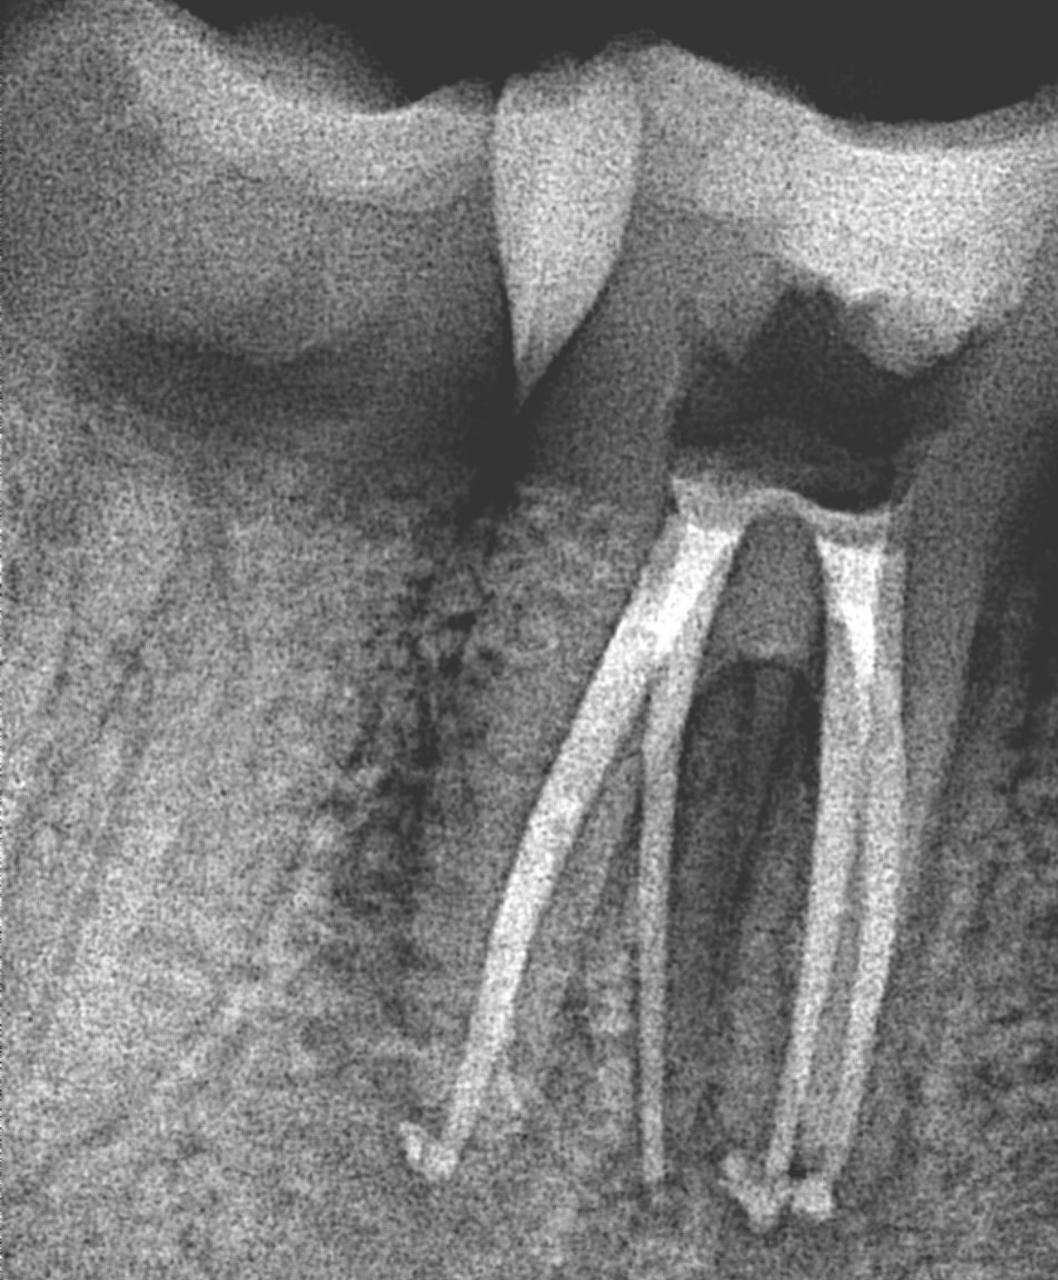

2. What Condition can be seen in this X ray regarding the tooth # 4.4.?